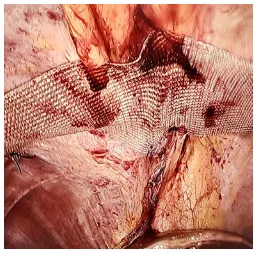

During surgery, the contents of the hernia sac, the stomach, the colon, and the left lobe of the liver, were reduced into the abdominal cavity. The falciform ligament was divided. The defect in the diaphragm was present anterior to the esophagus just behind the sternum, suggesting Morgagni’s hernia. The hernia defect was anatomically closed using intermittent sutures of 1-0 prolene.

The repaired diaphragm was further reinforced using prolene mesh. The patient’s postoperative period was uneventful, and she was discharged on the third day after surgery.